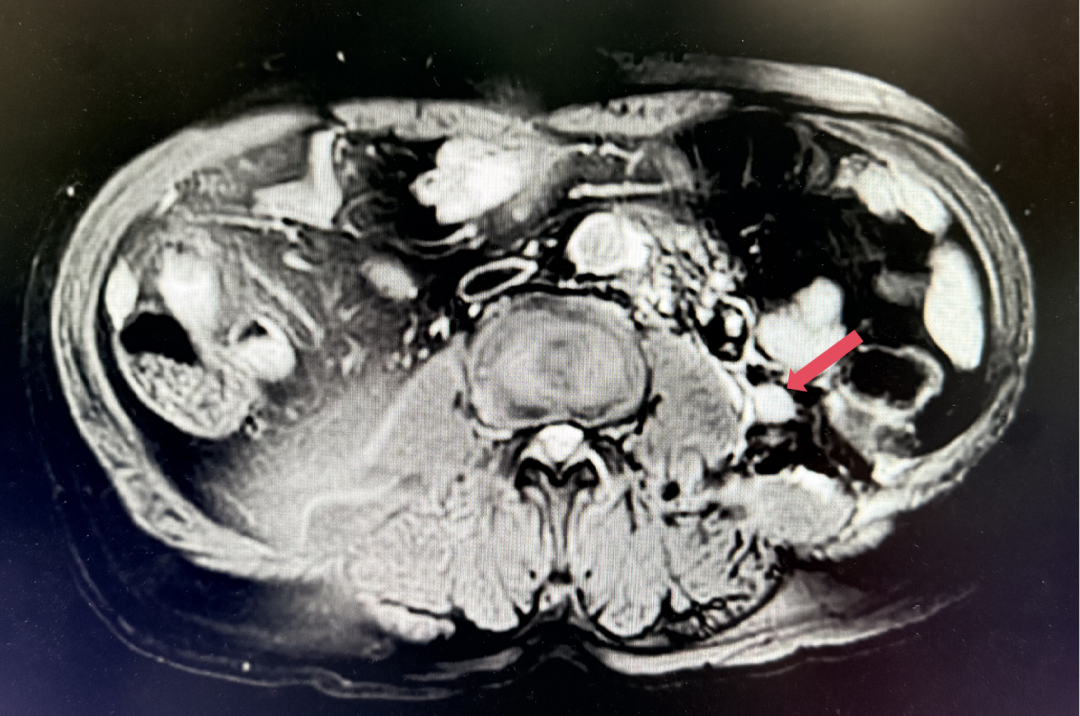

2023年11月:治疗10个月(C15)评估,肿瘤负荷减少至41mm,维持PR。

2023年11月,最深应答